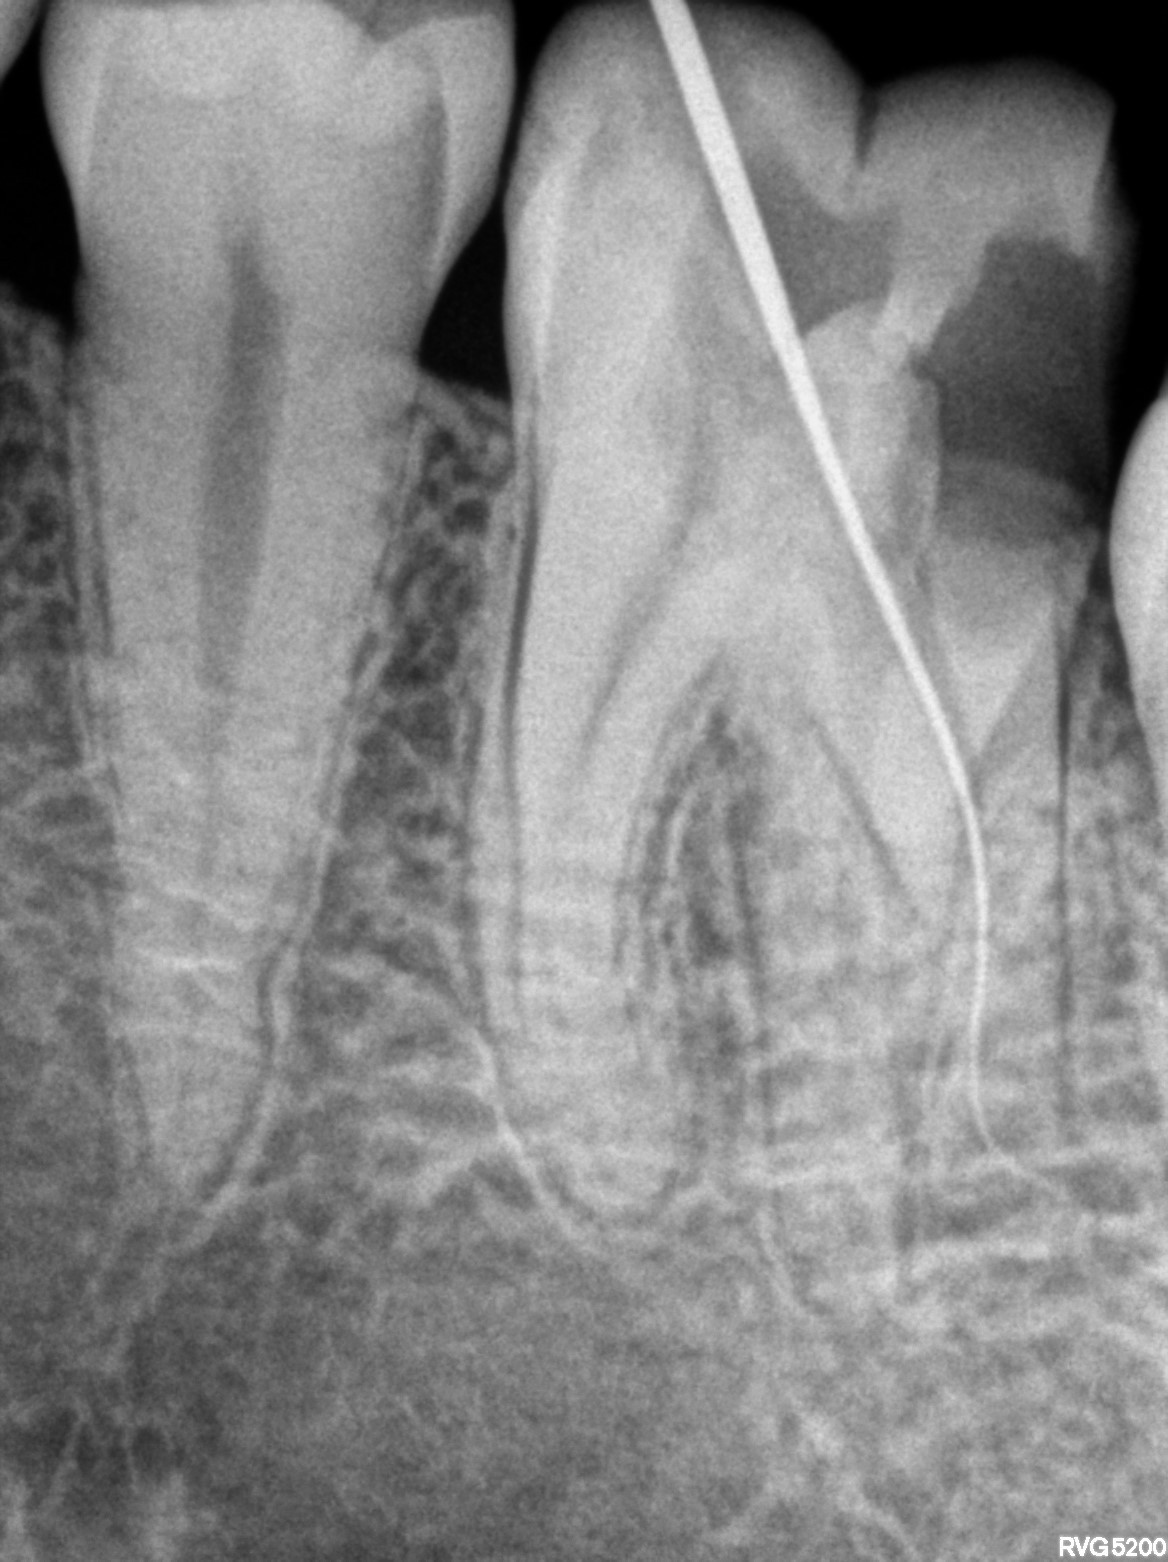

Dental Radiographs FHIR: DocumentReference · LOINC 24641-7

xray_1770998647_1.jpg

24641-7